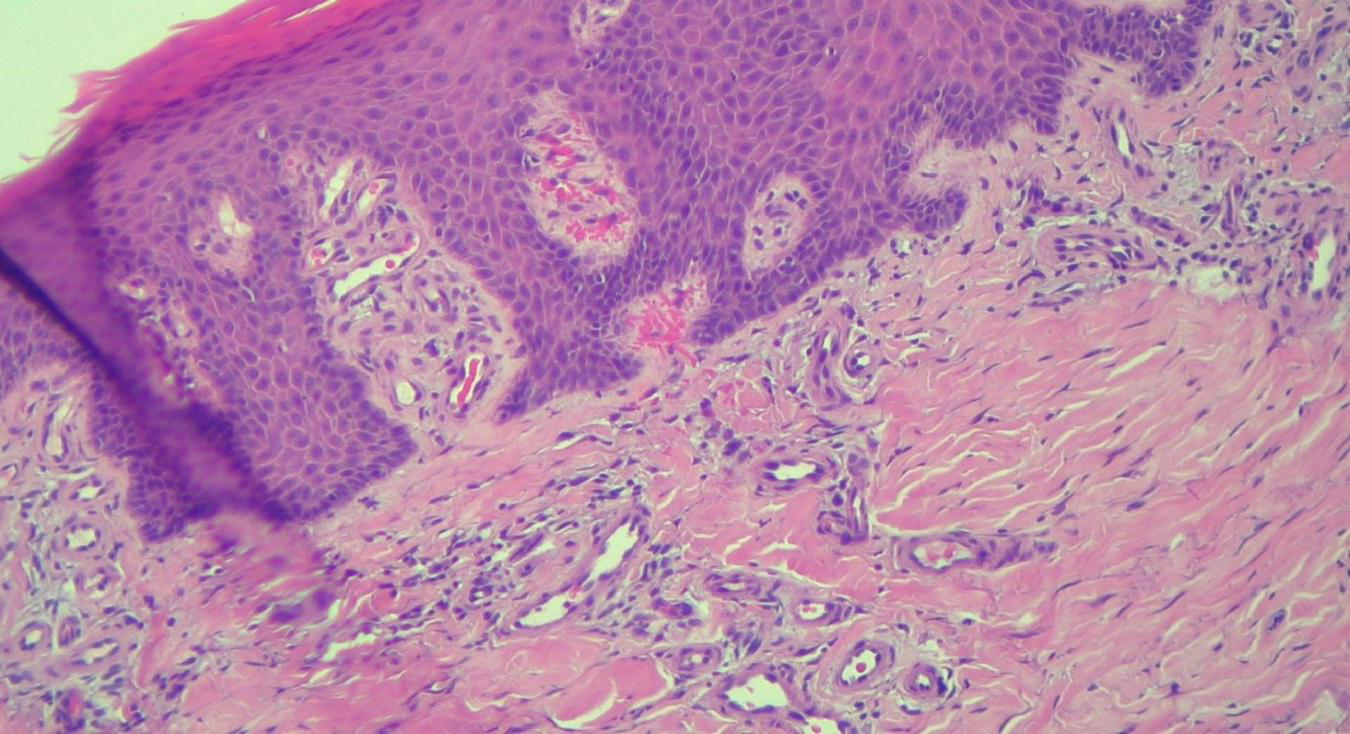

FIGURE 6

HEx100—Extreme tortuosity of dermal capillaries, extravasated erythrocytes.

The histopathological examination revealed (Figures 5–8). The examined skin fragment reveals an epidermis with marked hyperkeratosis, both ortho- and parakeratosis (confluent, with accumulations of neutrophils at this level—Munro microabscesses), a granular layer of variable thickness, with hypergranulosis and agranulosis, Kogoj pustules, regular psoriasiform acanthosis with elongated epidermal ridges, some rounded at the ends and fused at this level. The superficial dermis shows congested blood vessels, some with a tortuous appearance, and a perivascular inflammatory infiltrate consisting of lymphocytes, histiocytes, neutrophils (minimal), and extravasated red blood cells. Areas of erythrocyte exocytosis are also observed at the epidermal level.